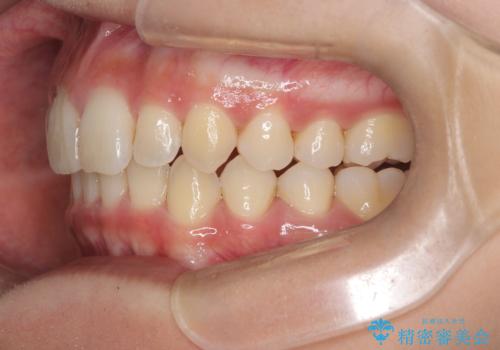

ディープバイト改善のためのインビザライン治療

- 患者様は、全体的な歯列のガタガタとディープバイト(深い噛み合わせ)を主訴として来院されました。診断の結果、ディープバイトを改善するためには、歯列全体の拡大が必要であると判断しました。治療には、透明なマウスピース型矯正装置「インビザライン」を使用し、歯を適切に拡大しながら歯並びを整える計画を立てました。治療期間はおおよそ2年を見込んで進め、最終的に見た目にも大きく変化をもたらすことを目指しました。

ディープバイトの治療には、奥歯の高さや前歯の位置に対する繊細な調整が必要です。本症例では、インビザラインによる歯列拡大を行うことで、噛み合わせを改善し、歯並び全体を整えました。治療過程では、歯間のスペースを確保するため、IPR(インタープロキシマルリダクション)を適宜行い、無理なく歯列の調整を行いました。治療後は、歯並びが大きく改善され、患者様の見た目にも大きな変化が現れました。インビザラインは透明で目立たず、治療中の見た目を気にされる患者様にも配慮した治療法です。